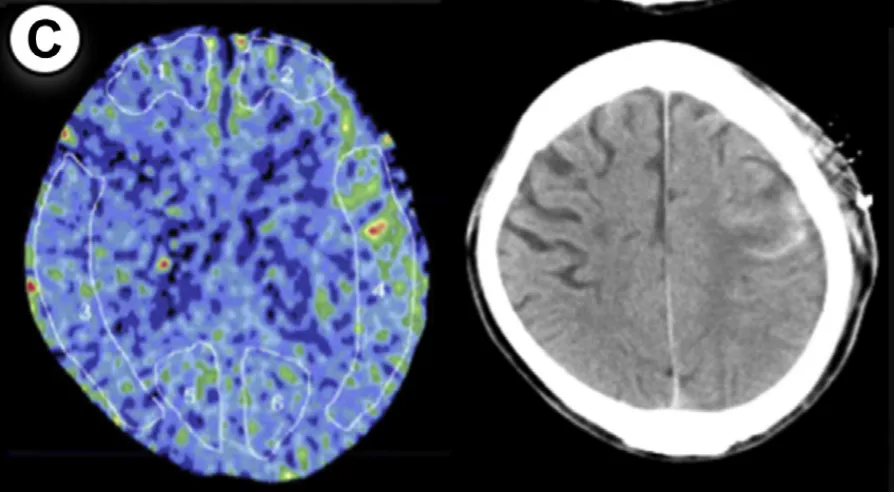

55岁男性,因颅内出血确诊烟雾病,行右侧大脑手术。方法1显示rCBF增加率47%,方法2为55%(超过50%阈值)。术后第3天中断镇静,第2天发生脑出血,改良Rankin量表评分恶化。

7例病例年龄范围25-55岁,出血类型包括脑出血(ICH)、蛛网膜下腔出血(SAH)、硬膜下血肿(SDH)及混合出血,发病时间集中于术后1-5天。所有病例rCBF增加率均超过阈值,证实了预警系统的可靠性。

通过氙气增强CT,在大脑中动脉供血区固定部位测量rCBF,术后即时完成首次检测。